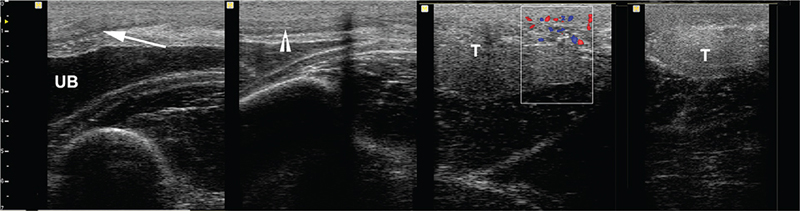

The retained testis can be recognized by the characteristic hyperechoic appearance of the tunica albuginea and the presence of a central vein104,107 (Figures 16). An inguinal retained testis is often misshapen and has a less echogenic parenchyma than normal scrotal testis. The superficial inguinal and deep inguinal cryptorchid testis can be accurately localized in 100% and 93% of the cases respectively.108,109 In one report that included 127 horses with 141 cryptorchid testes, the sensitivity and specificity of percutaneous inguinal ultrasonography to determine the location of the testis were 98% and 97%, respectively.110

Fig. 16.

Figure 16. Ultrasonogram of an inguinal testis (T). Note the hyperechoic albuginea (arrow).

Abdominal testes are often visualized on the ventral abdominal wall within a few centimeters of or adjacent to the urinary bladder (Figures 17, 18) and lying between the intestinal loops or colon haustra. Left abdominal testis are more difficult to visualize. They may be found between the left ventral colon and the spleen. Other factors that may hinder visualization of the abdominal testes include higher location due to short testicular cord, gas, or food-filled large colon. Examination of the horse after a period of 24 to 36 hours fasting may improve ultrasonographic localization of the abdominal testis.104

Fig. 17.

Figure 17. Ultrasonogram of abdominal testis testis (T) showing clearly an anechoic area corresponding to the central vein (top arrow), and a teratoma.

Fig. 18.

Figure 18. Examples of ultrasonograms of abdominal testes visualized by abdominal scanning (T = testis, UB = urinary bladder, arrow indicates intestinal loops).

The combination of inguinal and abdominal ultrasonographic examination allow location of the testes with very high sensitivity (97.6%) and specificity (100%).104,111 However, some authors reported only a 50% localization of incomplete abdominal testis with a specificity of 75%.109 Other authors reported localization of the abdominal testis in 72.7% of the cases.108 This difference of results may be due to a difference in experience and/or type of horses examined, gas or content in the large colon.